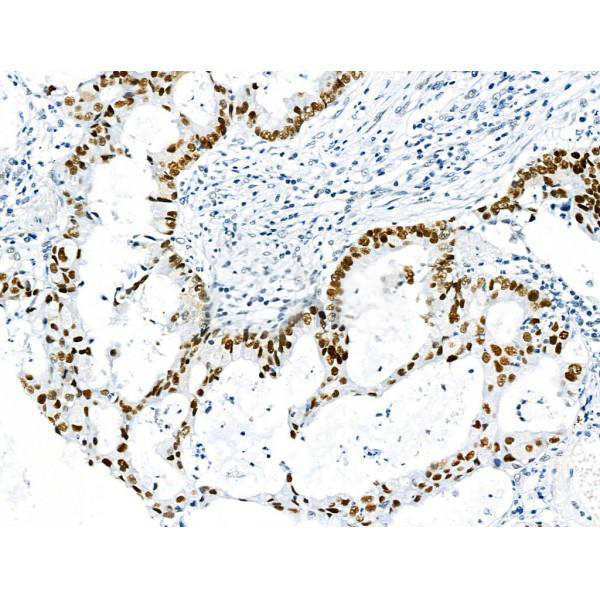

p53, Polyclonal Antibody (Cat# AAA31355)

Predicted Reactivity: Rabbit (90%), Dog (100%)

p53, Polyclonal Antibody (Cat# AAA31429)

Predicted Reactivity: Pig (88%), Bovine (88%), Sheep (88%), Rabbit (88%)

p53, Polyclonal Antibody (Cat# AAA31354)

Predicted Reactivity: Pig (91%), Sheep (80%), Rabbit (91%), Dog (91%)

p53, Polyclonal Antibody (Cat# AAA31377)

Predicted Reactivity: Pig (91%), Sheep (80%), Rabbit (91%), Dog (91%)